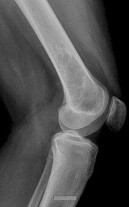

Question 8

A 15-year-old male presents with deep knee pain awakening him at night. Radiographs show a permeative destructive lesion in the distal femoral metaphysis with a 'sunburst' periosteal reaction and Codman's triangle.

Biopsy confirms high-grade conventional osteosarcoma. What is the most critical prognostic factor for long-term overall survival in this patient?

Explanation

For localized high-grade osteosarcoma, the most important prognostic indicator is the histologic response to neoadjuvant chemotherapy. This is evaluated during the definitive resection. A 'good response' is typically defined as greater than 90% or 99% tumor necrosis. Patients who achieve this level of necrosis have a significantly improved disease-free and overall survival rate compared to 'poor responders' who have extensive viable tumor cells remaining.